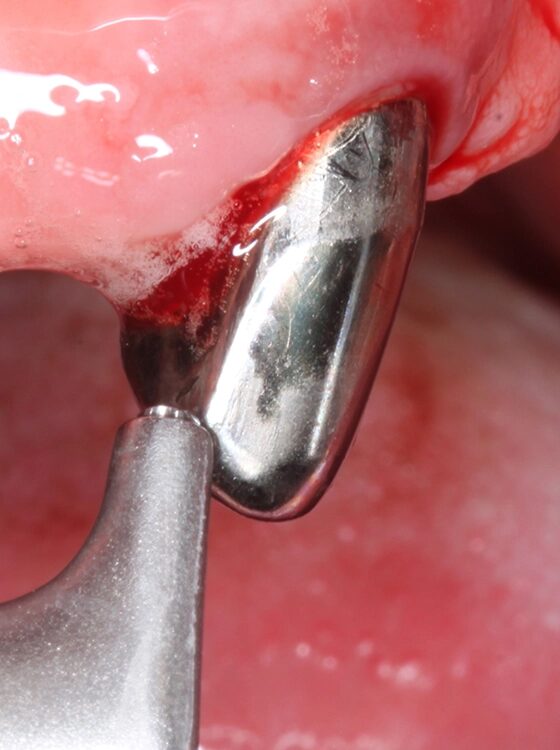

Abb. 4 a–j: Mögliche Variante des schrittweisen klinischen Vorgehens zur Anwendung von Straumann® Emdogain® im Rahmen einer initialen NCPT an Zahn 23. a)Initiale Sondierungstiefe, b) nach der Applikation der Lokalanästhesie erfolgt die subgingivale Instrumentierung mit Ultraschall und c) Pulverwasserstrahlgemischen (AIRFLOW® PLUS Pulver, EMS, Nyon, Schweiz), d) Spülung mit H2O2 3%, e) Spülung mit physiologischer Kochsalzlösung, f) Applikation einer konditionierenden EDTA-Lösung (Straumann® PrefGel®, Straumann Group, Basel, Schweiz), g) Trocknung und Blutstillung durch Einbringen von sterilisiertem Superfloss, h) Zahn 23 vorbereitet für die Applikation von SMP (Straumann® Emdogain®, Straumann Group, Basel, Schweiz), i) Applikation von Straumann® Emdogain®, j) Applikation von Histoacryl® Gewebekleber (B. Braun, Tuttlingen, Deutschland)Walter

Abb. 4 a–j: Mögliche Variante des schrittweisen klinischen Vorgehens zur Anwendung von Straumann® Emdogain® im Rahmen einer initialen NCPT an Zahn 23. a)Initiale Sondierungstiefe, b) nach der Applikation der Lokalanästhesie erfolgt die subgingivale Instrumentierung mit Ultraschall und c) Pulverwasserstrahlgemischen (AIRFLOW® PLUS Pulver, EMS, Nyon, Schweiz), d) Spülung mit H2O2 3%, e) Spülung mit physiologischer Kochsalzlösung, f) Applikation einer konditionierenden EDTA-Lösung (Straumann® PrefGel®, Straumann Group, Basel, Schweiz), g) Trocknung und Blutstillung durch Einbringen von sterilisiertem Superfloss, h) Zahn 23 vorbereitet für die Applikation von SMP (Straumann® Emdogain®, Straumann Group, Basel, Schweiz), i) Applikation von Straumann® Emdogain®, j) Applikation von Histoacryl® Gewebekleber (B. Braun, Tuttlingen, Deutschland)

Der Patient wurde über die Krankheitsentstehung, die Prognosen der Einzelzähne und die therapeutischen Optionen aufgeklärt. Es wurde eine systematische parodontale Therapie unter Berücksichtigung der aktuellen EFP/ DGParo-Leitlinien geplant [48]. Der radiologisch sichtbare Knochenverlust an den Zähnen 37 und 47 ging bereits weit über den Apex hinaus. Eine parodontale Therapie erschien daher nicht mehr erfolgversprechend. Die Zähne wurden vor der antiinfektiösen Therapie (AIT) extrahiert und die Alveolen mit adaptierenden Nähten stabilisiert. Im Rahmen der Unterweisungen für eine optimierte häusliche Mundhygiene wurde dem Patienten die Benutzung einer Monobüschelbürste demonstriert und empfohlen. Bei regelmäßiger Anwendung an den vereinzelten, mit Primärteleskopen versorgten Zähnen lassen sich auch diese Zähne in ihrer gesamten Zirkumferenz sehr gut reinigen. Bei den verbliebenen 5 Zähnen war geplant, die zur Verfügung stehenden nichtchirurgischen Möglichkeiten auszuschöpfen. Eine adjuvante Gabe von systemischen Antibiotika war allerdings nicht vorgesehen. Das bedeutete aber, dass im Oberkiefer an den besonders schwer vorgeschädigten Zähnen 13 und 23 neben der subgingivalen Instrumentierung mit Ultraschall und Pulverwasserstrahl (EMS, Nyon, Schweiz) zusätzlich SMP (Straumann® Emdogain®, Basel, Schweiz) appliziert werden sollten [50]. Da beide Zähne einen erhöhten Lockerungsgrad aufwiesen, bestünde die Notwendigkeit einer präoperativen Schienung spätestens vor einer möglichen chirurgischen Stufe-3-Therapie.

Der Punkt, dass beide Zähne demzufolge wohl eher nicht unter optimalen Bedingungen parodontalchirurgisch operiert werden können, hat daher auch zu der Entscheidung einer SMP/EMD-Anwendung in der AIT beigetragen. Die AIT wurde an einem Termin durchgeführt. Nach der Applikation einer Lokalanästhesie wurden alle Zähne zunächst mit Ultraschall und nach Detektion glatter und harter Wurzeloberflächen mit einem erythritolhaltigen Pulverwasserstrahlgemisch mit dem Standard-Handstück behandelt (EMS, Nyon, Schweiz). An den Zähnen 13 und 23 wurden in derselben Sitzung noch zusätzlich SMP – entsprechend einem von Prof. A. Kašaj publiziertem Protokoll (Abb. 5) – appliziert. Zuvor wurde eine Blutstillung unter Verwendung von H2O2 und dem Einbringen von sterilisiertem Superfloss vorgenommen und ein EDTA-Gel zur Konditionierung der Wurzeloberfläche appliziert. Das Aufbringen von Histoacryl® (B. Braun, Tuttlingen, Deutschland) Gewebekleber zum Verschluss der instrumentierten parodontalen „Taschen“ rundete diesen Behandlungszyklus ab. Das detaillierte Vorgehen bei diesem Patienten ist in den Abbildungen 4a–j dargestellt. Da die Zähne nicht geschient werden konnten, wurde der Patient instruiert, auf ein Herausnehmen und Wiedereinsetzen der Prothese sofern möglich in den nächsten Tagen zu verzichten. Nach der AIT wurde die supragingivale Plaquekontrolle an 3 Terminen kontrolliert und die Wundheilung durch professionelle Zahnreinigungen unterstützt.